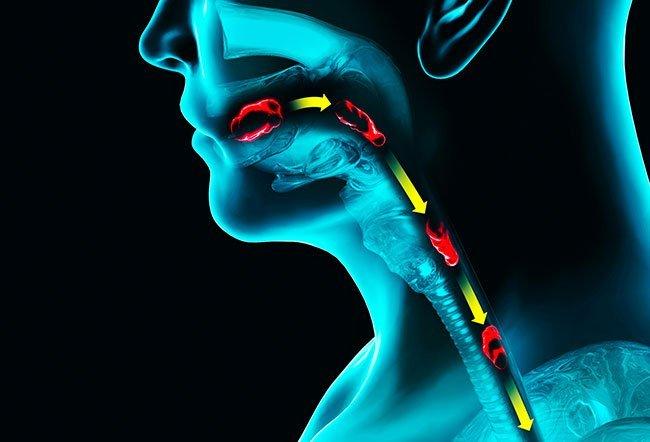

ENT Clinic in Rahatani,Kalewadi,Pimple Saudagar,PCMCENT Surgeon,ENT Doctor in Rahatani,Kalewadi,Pimple Saudagar,PCMCENT Specialist,ENT Surgeon in Rahatani,Kalewadi,Pimple Saudagar,PCMCEar Cleaning Clinic in Rahatani,Kalewadi,Pimple Saudagar,PCMCEar Lobe Repair Clinic in Rahatani,Kalewadi,Pimple Saudagar,PCMCEar Nose Piercing Clinic in Rahatani,Kalewadi,Pimple Saudagar,PCMCKeloid Excision Clinic in Rahatani,Kalewadi,Pimple Saudagar,PCMCHearing Evaluation Clinic in Rahatani,Kalewadi,Pimple Saudagar,PCMCHearing Aid Clinic in Rahatani,Kalewadi,Pimple Saudagar,PCMCTympanoplasty Clinic in Rahatani,Kalewadi,Pimple Saudagar,PCMCHeadache and Vertigo Evaluation Clinic in Rahatani,Kalewadi,Pimple Saudagar,PCMCNasal And Laryngeal Endoscopy Clinic in Rahatani,Kalewadi,Pimple Saudagar,PCMCAllergy Test-Skin Prick Test Clinic in Rahatani,Kalewadi,Pimple Saudagar,PCMCSeptoplasty Clinic in Rahatani,Kalewadi,Pimple Saudagar,PCMCSinusitis Treatment Clinic in Rahatani,Kalewadi,Pimple Saudagar,PCMCEndoscopic Sinus Surgery Clinic in Rahatani,Kalewadi,Pimple Saudagar,PCMCEndoscopic DCR Clinic in Pimple Saudagar,PCMCMucormycosis Diagnosis And Treatment Clinic in Rahatani,Kalewadi,Pimple Saudagar,PCMCTonsillectomy Treatment Clinic in Rahatani,Kalewadi,Pimple Saudagar,PCMCEvaluation of Voice Change And Difficulty in Swallowing Clinic in Pimple Saudagar,PCMCAdenoid Surgery Clinic in Rahatani,Kalewadi,Pimple Saudagar,PCMCEvaluation of Neck Swelling (Thyroid) Clinic in Rahatani,Kalewadi,Pimple Saudagar,PCMCThyroid Surgery Treatment in Rahatani,Kalewadi,Pimple Saudagar,PCMCDiagnosis of Head And Neck Cancers Treatment in Rahatani,Kalewadi,Pimple Saudagar,PCMC